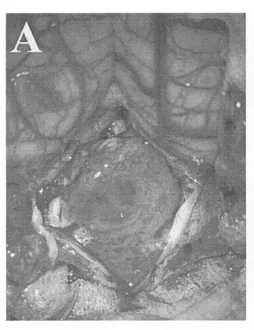

巴教授首先用CUSA刀为肿瘤“瘦身”,逐步为关键神经血管结构腾出空间。随后,在显微镜下完成了一场极致精细的“拆弹”手术:完整游离尾组颅神经根丝、椎动脉(VA)近端及PICA分支。

(A)硬脑膜切开后可见向下延伸至C1水平的大型肿瘤;

肿瘤已侵犯脑干,巴教授仍坚持在第四脑室底彻底切除肿瘤,以防复发,并进行细致的止血。因为研究表明,术后CT或MR影像学无肿瘤残留是长期生存的有利因素。